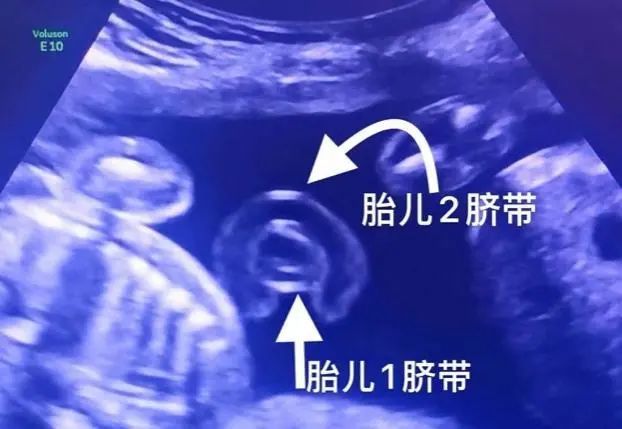

医院为一位双胞胎妈妈成功施行了双胎剖宫产,当宝宝脐带出来的那一刻

二胎妈妈产下双胞胎 两个孩子脐带缠成"中国结"

双胞胎脐带缠成"中国结",医生惊出了一身冷汗!